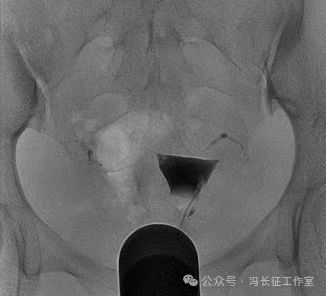

栓塞术后7个月于2015年1月做子宫输卵管造影复查看看栓塞效果

平片显示盆腔内2个C形高密度影为弹簧圈

微信图片_20240223171417(6).jpg

造影显示2个弹簧圈紧实固定在输卵管间质部和峡部近段。弹簧圈两端由于弹性回缩力的回缩呈C形,卡在输卵管内壁上,完全封闭管腔,造影剂未能进入通过栓塞段,栓塞段输卵管远端未能显影。